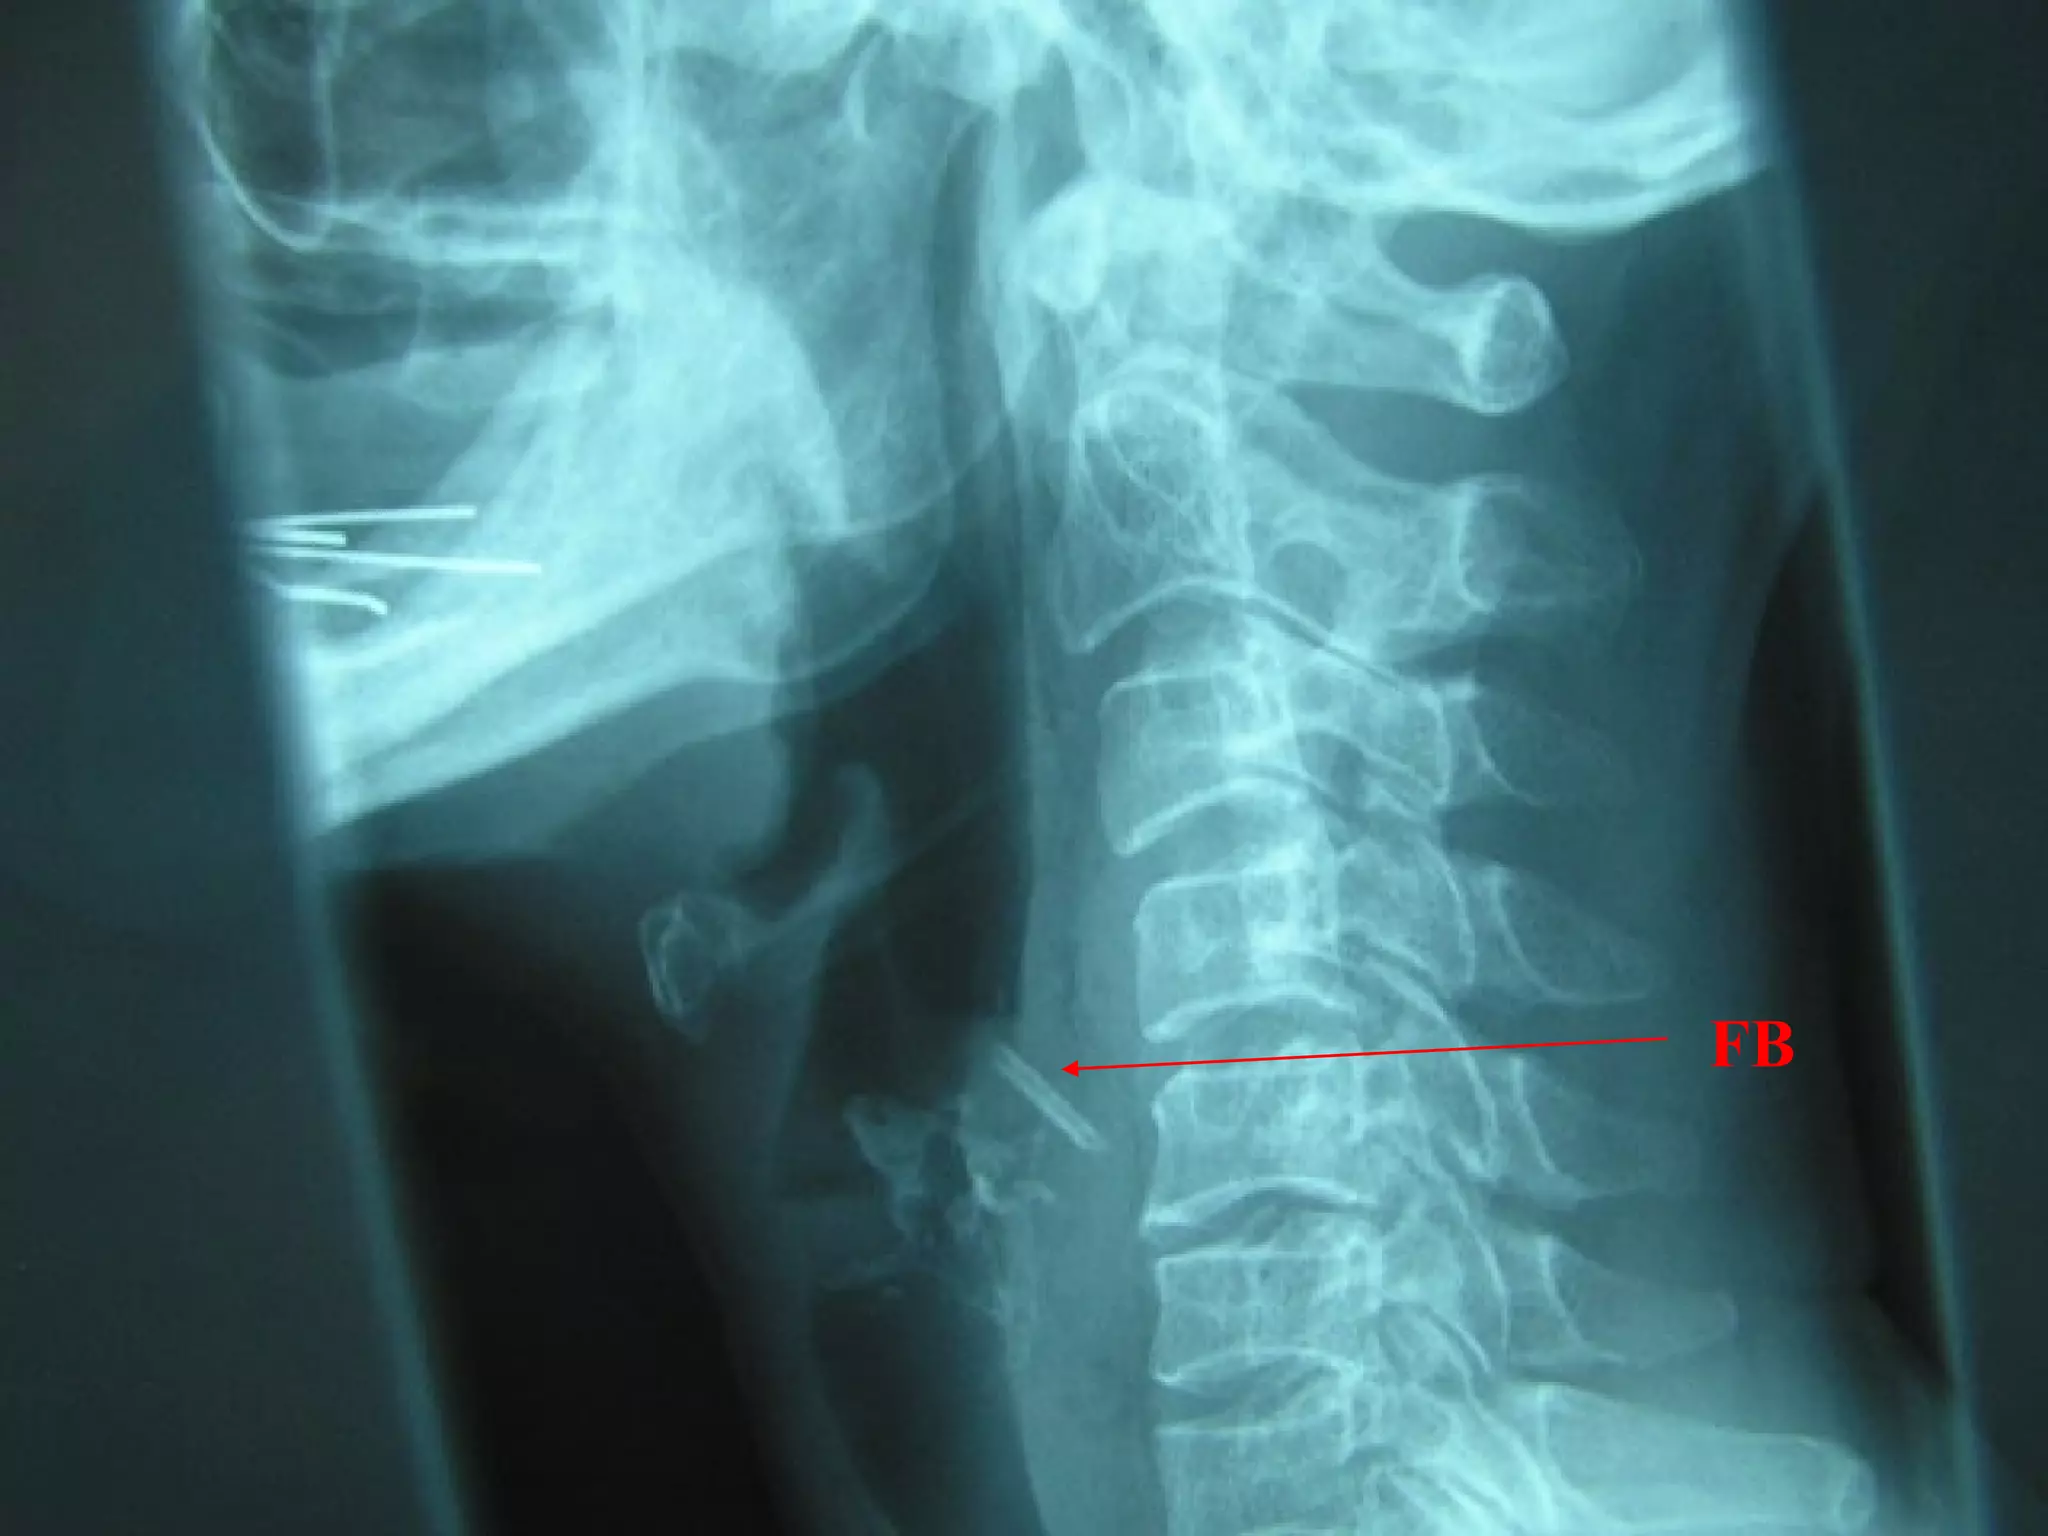

Deep Neck Infection

Neck swelling

Sore throat, odynophagia, trismus

Immunocompromised

Fever, unwell

Lateral neck XR

Airway control

Admission for CT, KIV I&D

Deep Neck

Infection

•Normal retropharyngeal

space on lateral neck XR is

up to 1 vertebral body

width from C5 and below.

Widened

retropharyngeal space

on lateral neck XR

•Up to half a vertebral

body width from C1 to C4

is normal